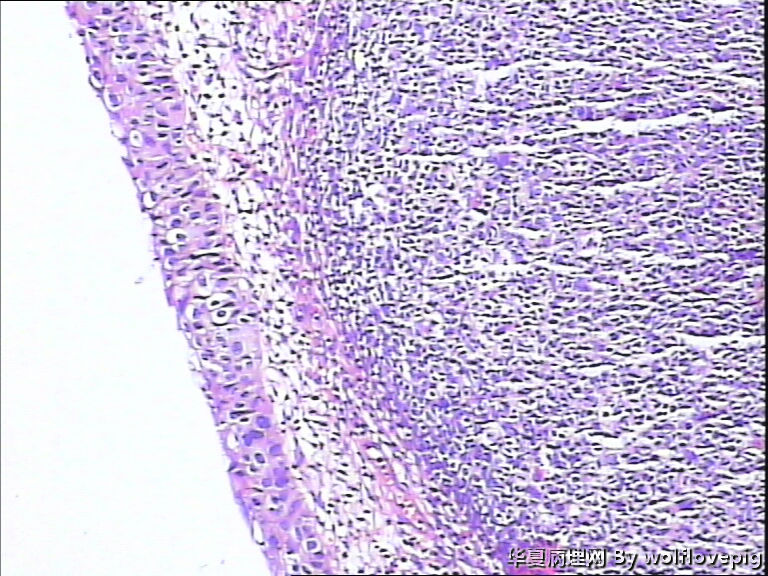

求助,宫颈!

37y

CIN3累腺

CINIII累及腺体

CIN2-3,累腺